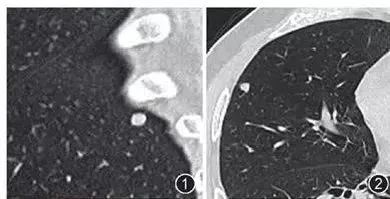

横看成岭侧成峰,下图CT扫描时显示的是叶间裂上的一个结节影(图1),而CT冠状面重建则显示该结节影其实为线状的疤痕或淋巴组织(图2)。